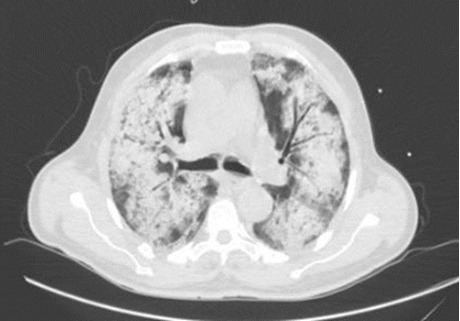

10月19日血滤时出现寒战,血压降低,夜间最高体温38.2℃。胸部CT示双肺多发渗出阴影较前好转(图5)

图5  胸部CT(10月19日)